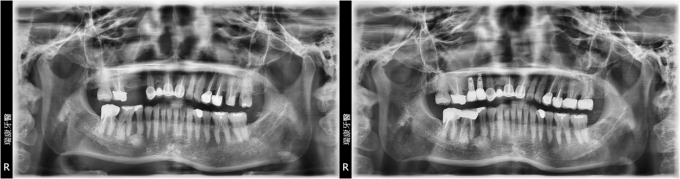

單顆缺牙人工植牙

病患莊先生,35年次,退休人員

主訴 : 右下後牙咬東西時劇痛

口腔檢查 : 右下牙齒斷裂

治療計劃 : 將右下後牙拔除後,等待三個月癒合期,進行人工植牙, 三個月後接出假牙基座印模製作正式假牙!

實例照片僅為資訊介紹及分享,效果可能因個人體質及保養方式不同而有所差異。